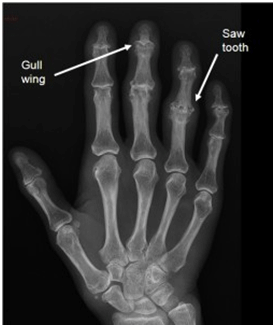

ΕΙΚΟΝΑ 1a. Τυπικές ακτινολογικές αλλοιώσεις ΔΟΑ : «Φτερά γλάρου» και διαβρώσεις τύπου «οδόντων πριονιού»

Η ΔOA χαρακτηρίζεται από την παρουσία διαβρώσεων συχνά σε συνδυασμό με οστική υπερπλασία, η οποία μπορεί να ποικίλλει σε έκταση. Τα κλασικά ακτινολογικά ευρήματα συνίστανται σε κεντρικές διαβρώσεις, κατάρρευση του υποχόνδριου ιστού και ενδοστικές οστικές συντήξεις (Ehrlich, 1972; McKendry, 1985). Στένωση του μεσάρθριου διαστήματος και υποχόνδρια σκλήρυνση παρατηρείται συχνά σε συνδυασμό με τα παραπάνω ευρήματα. Οι κεντρικές διαβρώσεις και οι επιχείλια οστεοφύτωση συχνά οδηγούν στη παραμόρφωση τύπου «φτερών γλάρου», που είναι και η ακτινολογική σφραγίδα της νόσου (Martel et al, 1980) (EIKONA 1a).

Αλλα ακτινολογικά ευρήματα

- Διαβρώσεις τύπου «οδόντων πριονιού» (EIKONA 1a), οι οποίες συχνά οδηγούν σε αγκύλωση (Greenspan, 2003).

Συγκριτικά με τις κεντρικές διαβρώσεις της ΔΟΑ, οι διαβρώσεις της ΡΑ τυπικά αναπτύσσονται στα όρια της άρθρωσης και δεν οδηγούν στην χαρακτηριστική εικόνα των «φτερών του γλάρου» που παρατηρείται στη ΔΟΑ. Η εικόνα αυτή δημιουργείται από κεντρικές διαβρώσεις στην εγγύς πλάκα, με επιχείλια υπερπλασία της περιφερικής πλάκας στις ΕΦΦ και ΑΦΦ αρθρώσεις.